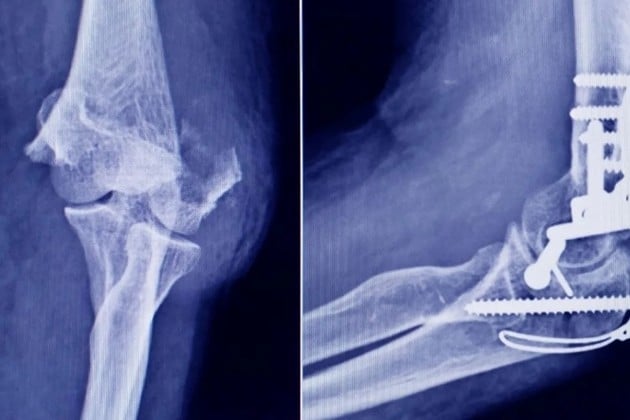

Frente a este escenario, la autoridad sanitaria dispuso la prohibición total del uso, comercialización y distribución de todos los productos involucrados.

La medida tiene carácter preventivo y busca evitar que estos insumos lleguen a ser utilizados en pacientes. Al mismo tiempo, se iniciaron actuaciones administrativas para determinar las responsabilidades del establecimiento inspeccionado.

Este tipo de procedimientos puede derivar en sanciones que van desde multas hasta la clausura del local, dependiendo de la gravedad de las irregularidades detectadas.